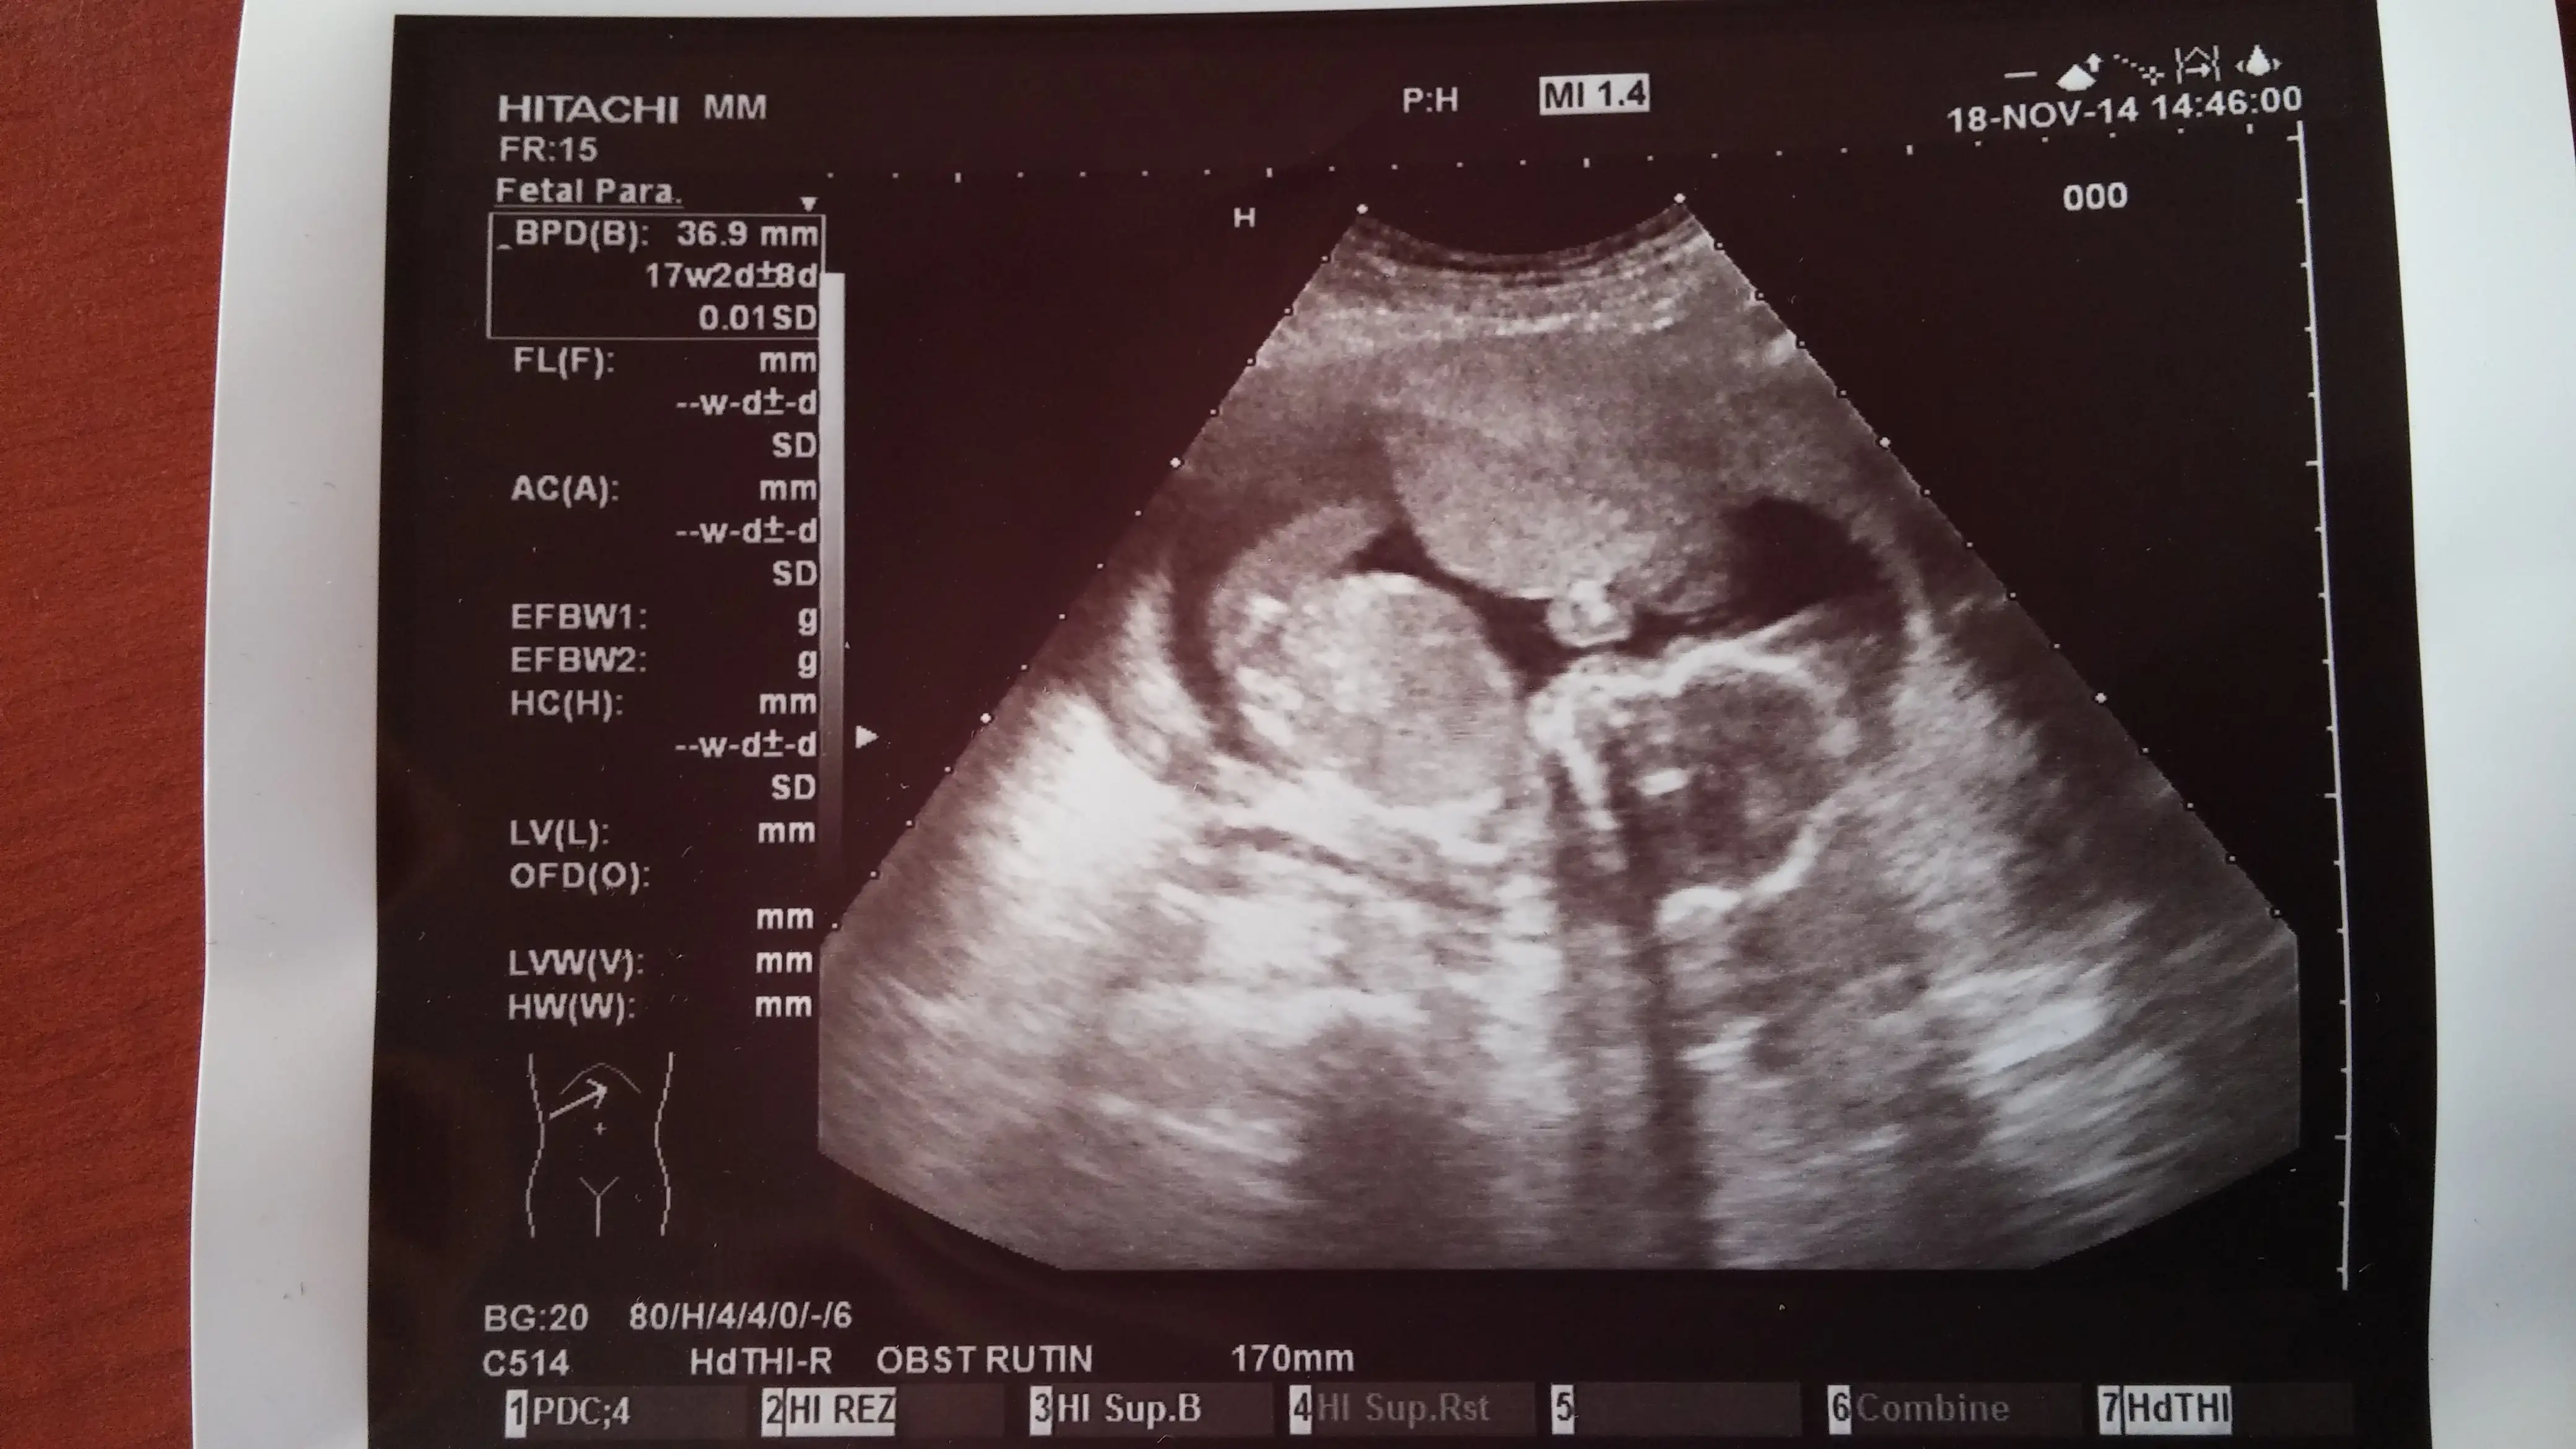

Bugun ayrintili ultrosonuma bakan dr.da kendini gostermiyo ama kiza benziyo sanki dedi. Gecen hafta dr.umda erkege benziyo demisti.hey allahim olucem meraktan.3 hafta daha beklicem simdi.bu resimlerdede belli olmuyo galiba???

• 20141118_173354.webp

20141118_173354.webp

180,7 KB · Görüntüleme: 149

• 20141118_173443.webp

20141118_173443.webp

163,2 KB · Görüntüleme: 159